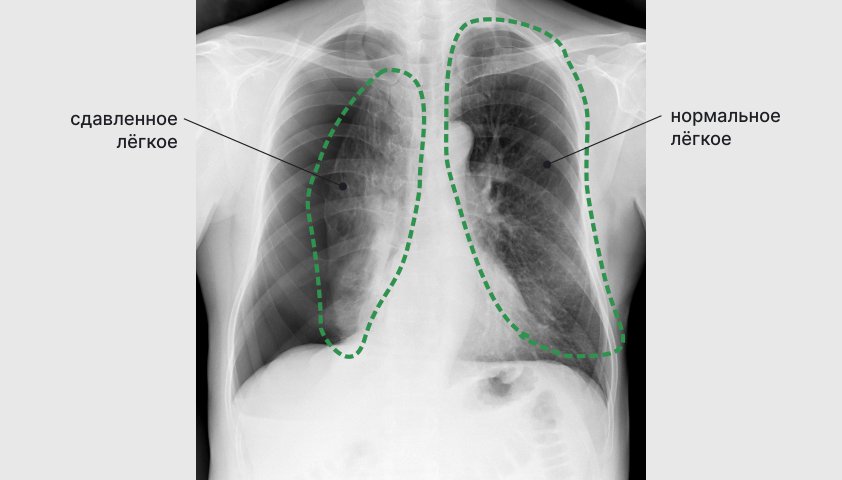

Следующий шаг — инструментальные методы диагностики. Врач может отправить пациента на рентген грудной клетки. В сомнительных случаях снимок делают на выдохе, так как пневмоторакс становится более заметным. Компьютерная томография (КТ) даёт более точную информацию о состоянии лёгких, наличии булл (патологических воздушных полостей) или других патологий.

Рентген грудной клетки в прямой и боковой проекции позволяет увидеть скопление воздуха и степень коллапса лёгкого

При пневмотораксе воздух проникает в герметичное пространство вокруг лёгкого — плевральную полость. Это приводит к сдавливанию дыхательного органа, из-за чего он не может полностью расправиться при вдохе. В результате нарушается дыхание, а в тяжёлых случаях может возникнуть угроза для жизни.

При пневмотораксе баланс давлений между плевральной полостью и лёгким нарушается — и оно опадает, как сдувшийся шарик

По степени коллапса лёгкого пневмоторакс делят на малый (когда лёгкое опало менее чем на треть), средний (до половины объёма) и большой (более половины). Тотальный пневмоторакс означает полное опадение лёгкого.